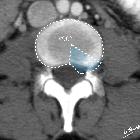

Disc protrusions are a type of disc herniation characterized by protrusion of disc content beyond the normal confines of the intervertebral disc, over a segment less than 25% of the circumference of the disc. The width of the base is wider than the largest diameter of the disc material which projects beyond the normal disc margins. The protrusion must not extend above or below the relevant vertebral endplates .

A disc protrusion is also described in terms of its axial position, into central, subarticular, foraminal, extraforaminal, or anterior locations .